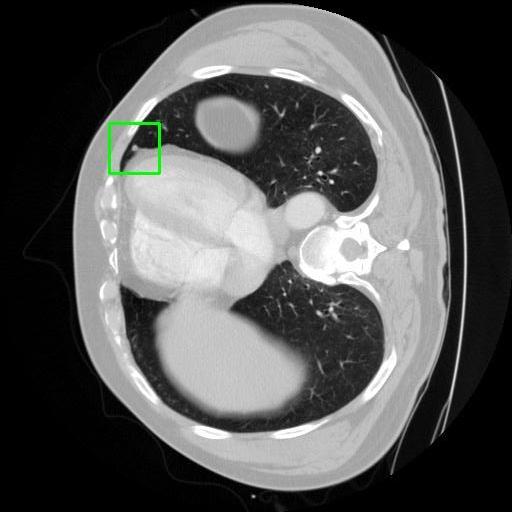

We developed an AI-based system using deep learning models for analyzing lung CT scans to detect and classify pulmonary nodules. We chose the YOLOv11 architecture for its enhanced object detection capability and adapted it specifically for medical imaging, incorporating pixel-level precision and severity classification.

Classification into three severity levels with colored bounding boxes.

Designed a severity classification system that categorizes nodules into null, moderate, and severe using colored bounding boxes, assisting in rapid clinical decision-making.